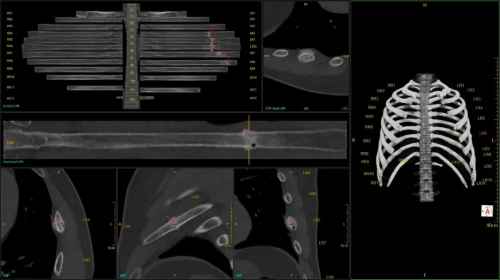

在卒中救治领域,无极系列CT配备的16cm宽体探测器,无需移床即可覆盖全脑,能够快速判断卒中类型。得益于该设备的协议快速切换能力,支持在缺血性脑卒中患者全脑灌注扫描中插入头颈CTA协议,60秒内便能完成全脑CTP+头颈CTA+全脑CTP的一站式扫描,一次操作即可采集全脑灌注数据及头颈CTA图像,获取包括脑实质解剖成像、脑血管及脑血流分布在内的全脑信息,大幅缩短了检查时间,让卒中救治分秒必争。

CTP+CTA+CTP一站式卒中扫描

灌注分析+核心梗死区与缺血半暗带量化分析

头颈CTA